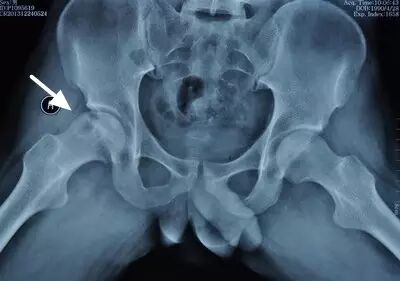

II期病人有髋部症状,磁共振出现异常,X线片显示股骨头出现透光和硬化改变

III期磁共振出现异常,X线片显示软骨下塌陷(新月征),股骨头内出现空洞,股骨头没有变扁

II期和III期的患者治疗方法相同,因为此时股骨头虽然还没有变形,暂时还不需要行人工关节置换术,但是股骨头已经出现空洞,随时股骨头就会塌陷变形,所以单纯的股骨头减压术是不能达到治疗效果的。这时就需要在股骨头减压的同时,植入一根支撑棒,顶住股骨头空洞区,防止股骨头在负重的情况下过早塌陷。其他治疗同之前相同,口服以上药物,定期复查,密切观察病情发展,尽量避免重体力劳动和爬山爬楼。

以上为股骨头坏死减压加支撑棒植入术示意图和术后X线片